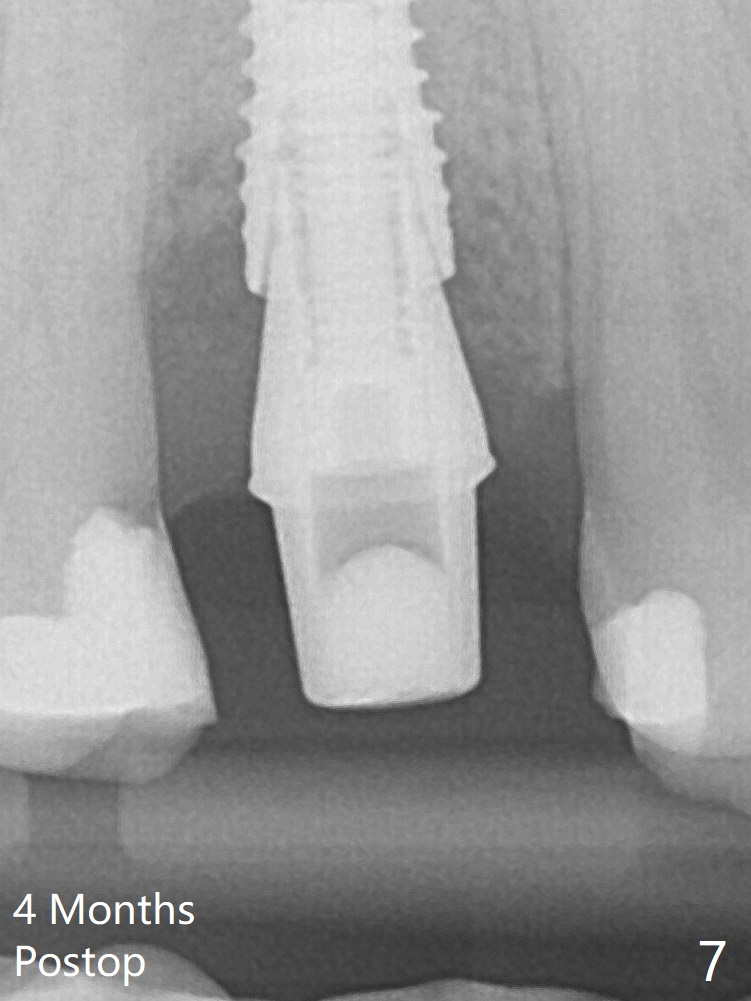

A 3.8x18 mm (definitive) implant is placed with <40 Ncm with the implant plateau apical to the lingual crest (Fig.4 (dashed line: upper border of the buccal defect)).  The buccal plate defect is repaired by Vanilla Graft (Fig.6 *) before and after insertion of a 4.5x4(3) mm abutment.  The buccal plate defect seems to being repaired 4 months postop (Fig.7).  The defect repair is close to completion 8 months post cementation (Fig.8).